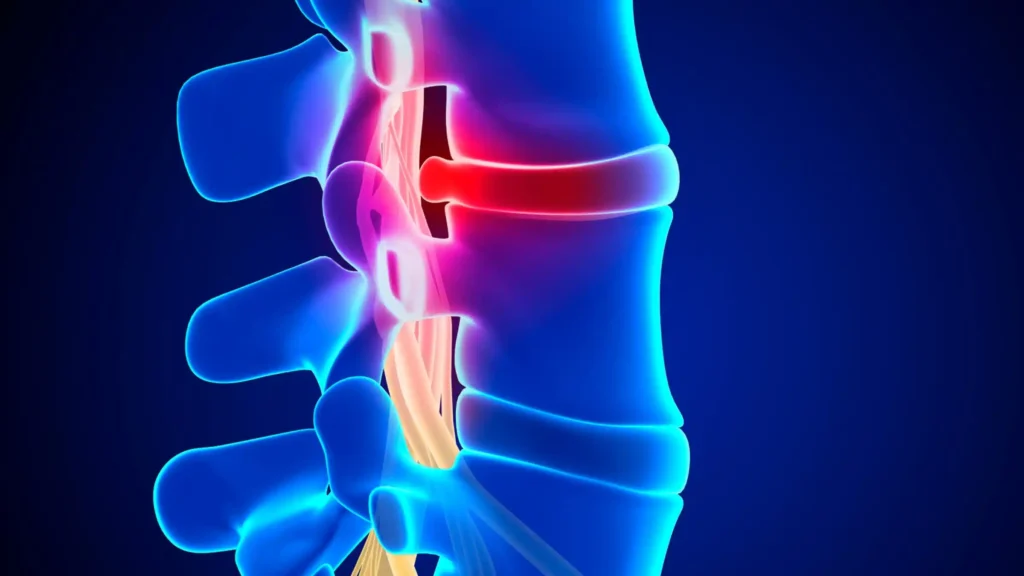

Lower Back Pain

Lower back pain is one of the most common reasons people seek medical care. Whether caused by injury, arthritis, or disc problems, Dr. Nwosu provides accurate diagnosis and effective treatment options, including non-surgical therapies and advanced minimally invasive procedures.

Common Causes:

Degenerative disc disease

Herniated lumbar discs

Poor posture or lifting injuries

Arthritis or spinal stenosis

Fractures or muscle strain

Symptoms:

Aching or shooting pain in the lower back

Leg numbness or tingling (sciatica)

Difficulty standing or walking

Muscle stiffness or weakness

Spinal Fusion & Motion Preservation

When the spine becomes unstable or severely degenerated, spinal fusion or motion-preserving technologies can restore strength and balance. Dr. Nwosu carefully evaluates each case to determine whether a fusion procedure or artificial disc replacement offers the best outcome.